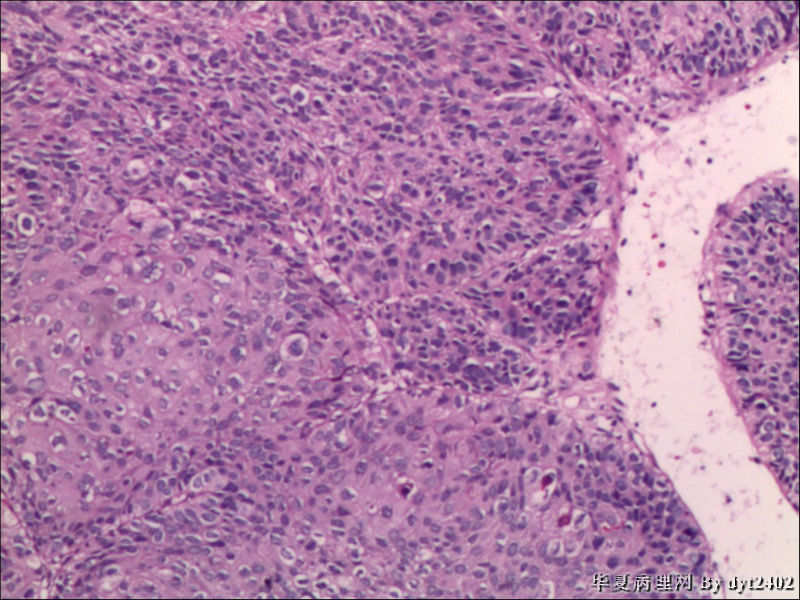

• 宫颈活检 其中一点较迷糊图1

图1

四点中三点是CIN iii,另一点怀疑有更重病变

这个病人是44岁,去年11月底阴道脱落细胞、TCT均见细胞异常,建议活检,病人犹豫,接着单位组织到外院体检时做阴道镜正常,后霉菌感染,此时宫颈未涂醋肉眼看还光滑,直至今年3月来做活检,事前做白带检查又见异常细胞,宫颈未涂醋见后上唇白上皮,涂醋酸后上下唇都有厚白上皮,镶嵌,夹活时上皮剥脱,未能夹到间质,阴道镜医生说至少有CIN III 到原位癌了。。镜下其中3点CIN III无疑,唯有9点处如6、7、11、14等所示结构,但我未见间质浸润,不能说是浸润癌,不知道有没基底细胞样鳞癌的可能,我发了个原位癌不除外深部有更重病变,。